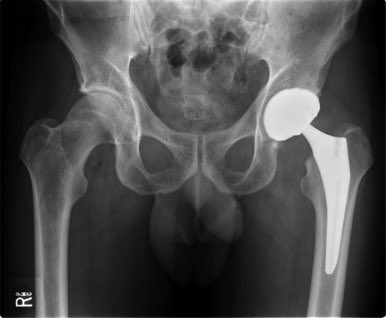

Лечение пертеса у детей

Лечение пертеса у детей 114 фотографий